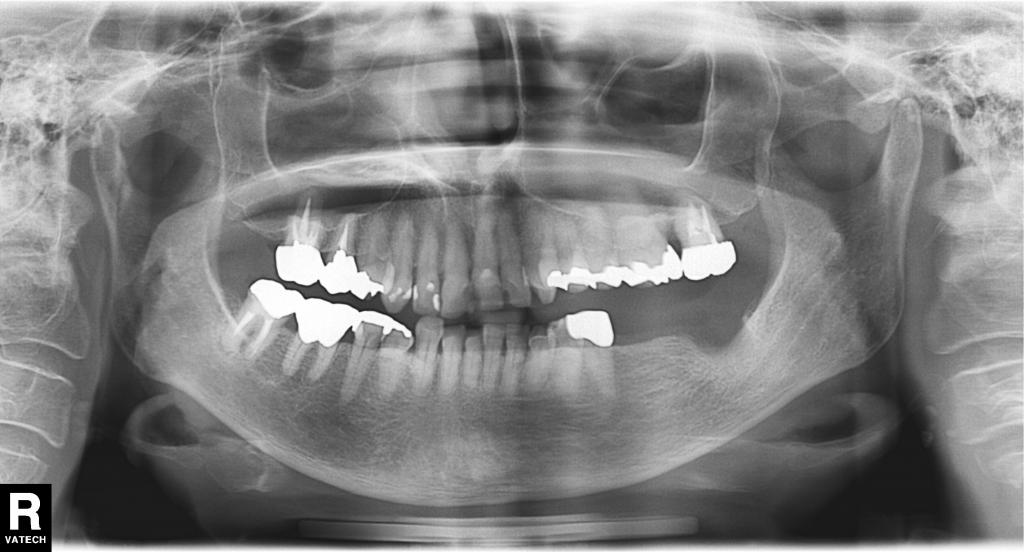

• インプラント治療事例にNO.62を掲載しました。

インプラント治療事例にNO.62を掲載しました。